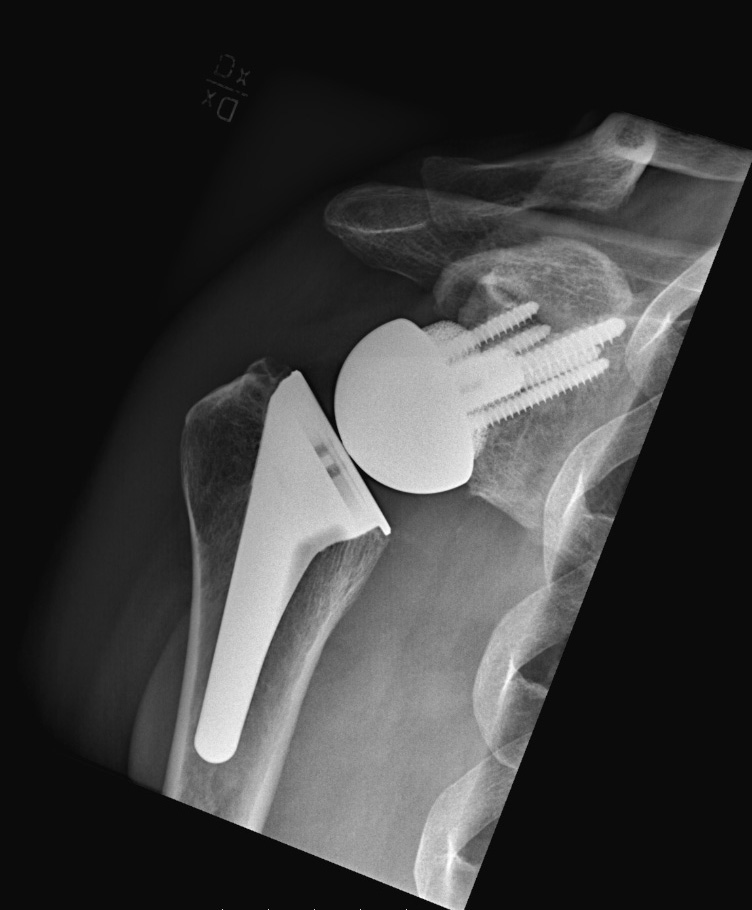

En omvänd totalprotes/omvänd frakturprotes liknar inte den normala anatomin, utan ledkomponenterna byter plats med varandra. Ledkulan fästs på skulderbladet och ledskålen på överarmen. Denna protes fungerar bra även om småmusklerna är trasiga och används ofta vid komplicerade frakturer.